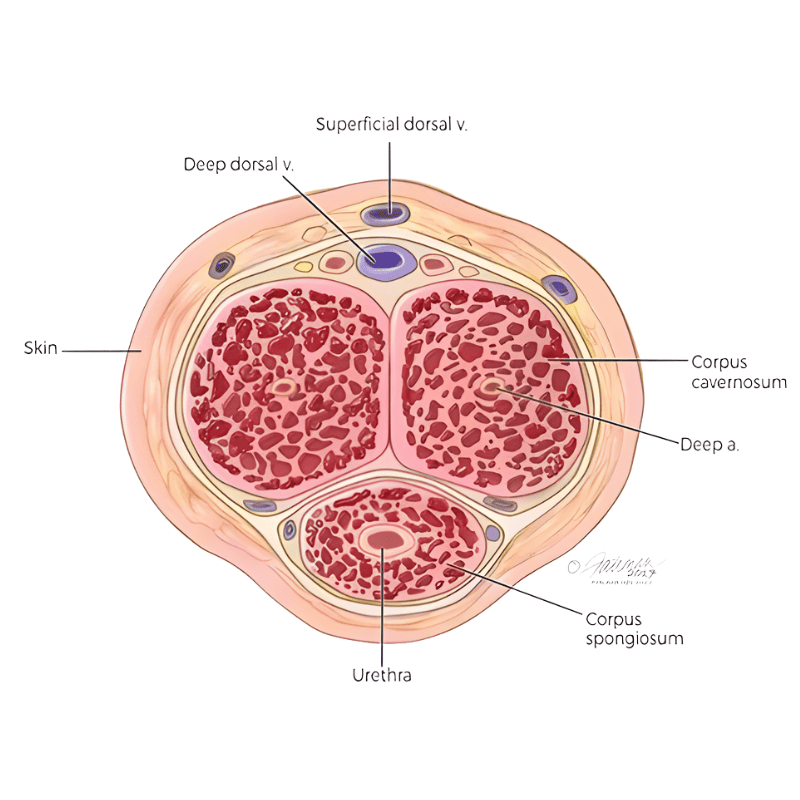

Melancarkan Darah Mikro Tisu Zakar

Sistem saluran darah halus yang bertindak sebagai pengisi, pengedar, dan pengering untuk memenuhi zakar dengan darah dan memerangkapnya di dalam, lalu menghasilkan ereksi.

Mengekalkan Keupayaan Mr. P

Krim menyerap ke rangkaian saluran mikro dan memenuhi semua ruang kosong dalam span tisu. Apabila span dipenuhi darah, ia mengembang seperti belon.

Saluran Arteri Level 1

Darah mengalir dengan lancar ke zakar. Boleh keras dengan mudah dan kekal keras dengan baik.

Saluran Arteri Level 2

Saluran darah sedikit tersumbat atau sempit. Zakar ambil masa lebih lama untuk keras.

Saluran Arteri Level 3

Saluran darah sangat sempit atau tersumbat. Sukar atau tidak boleh keras langsung, kalau boleh pun, ia lembik dan tak tahan lama